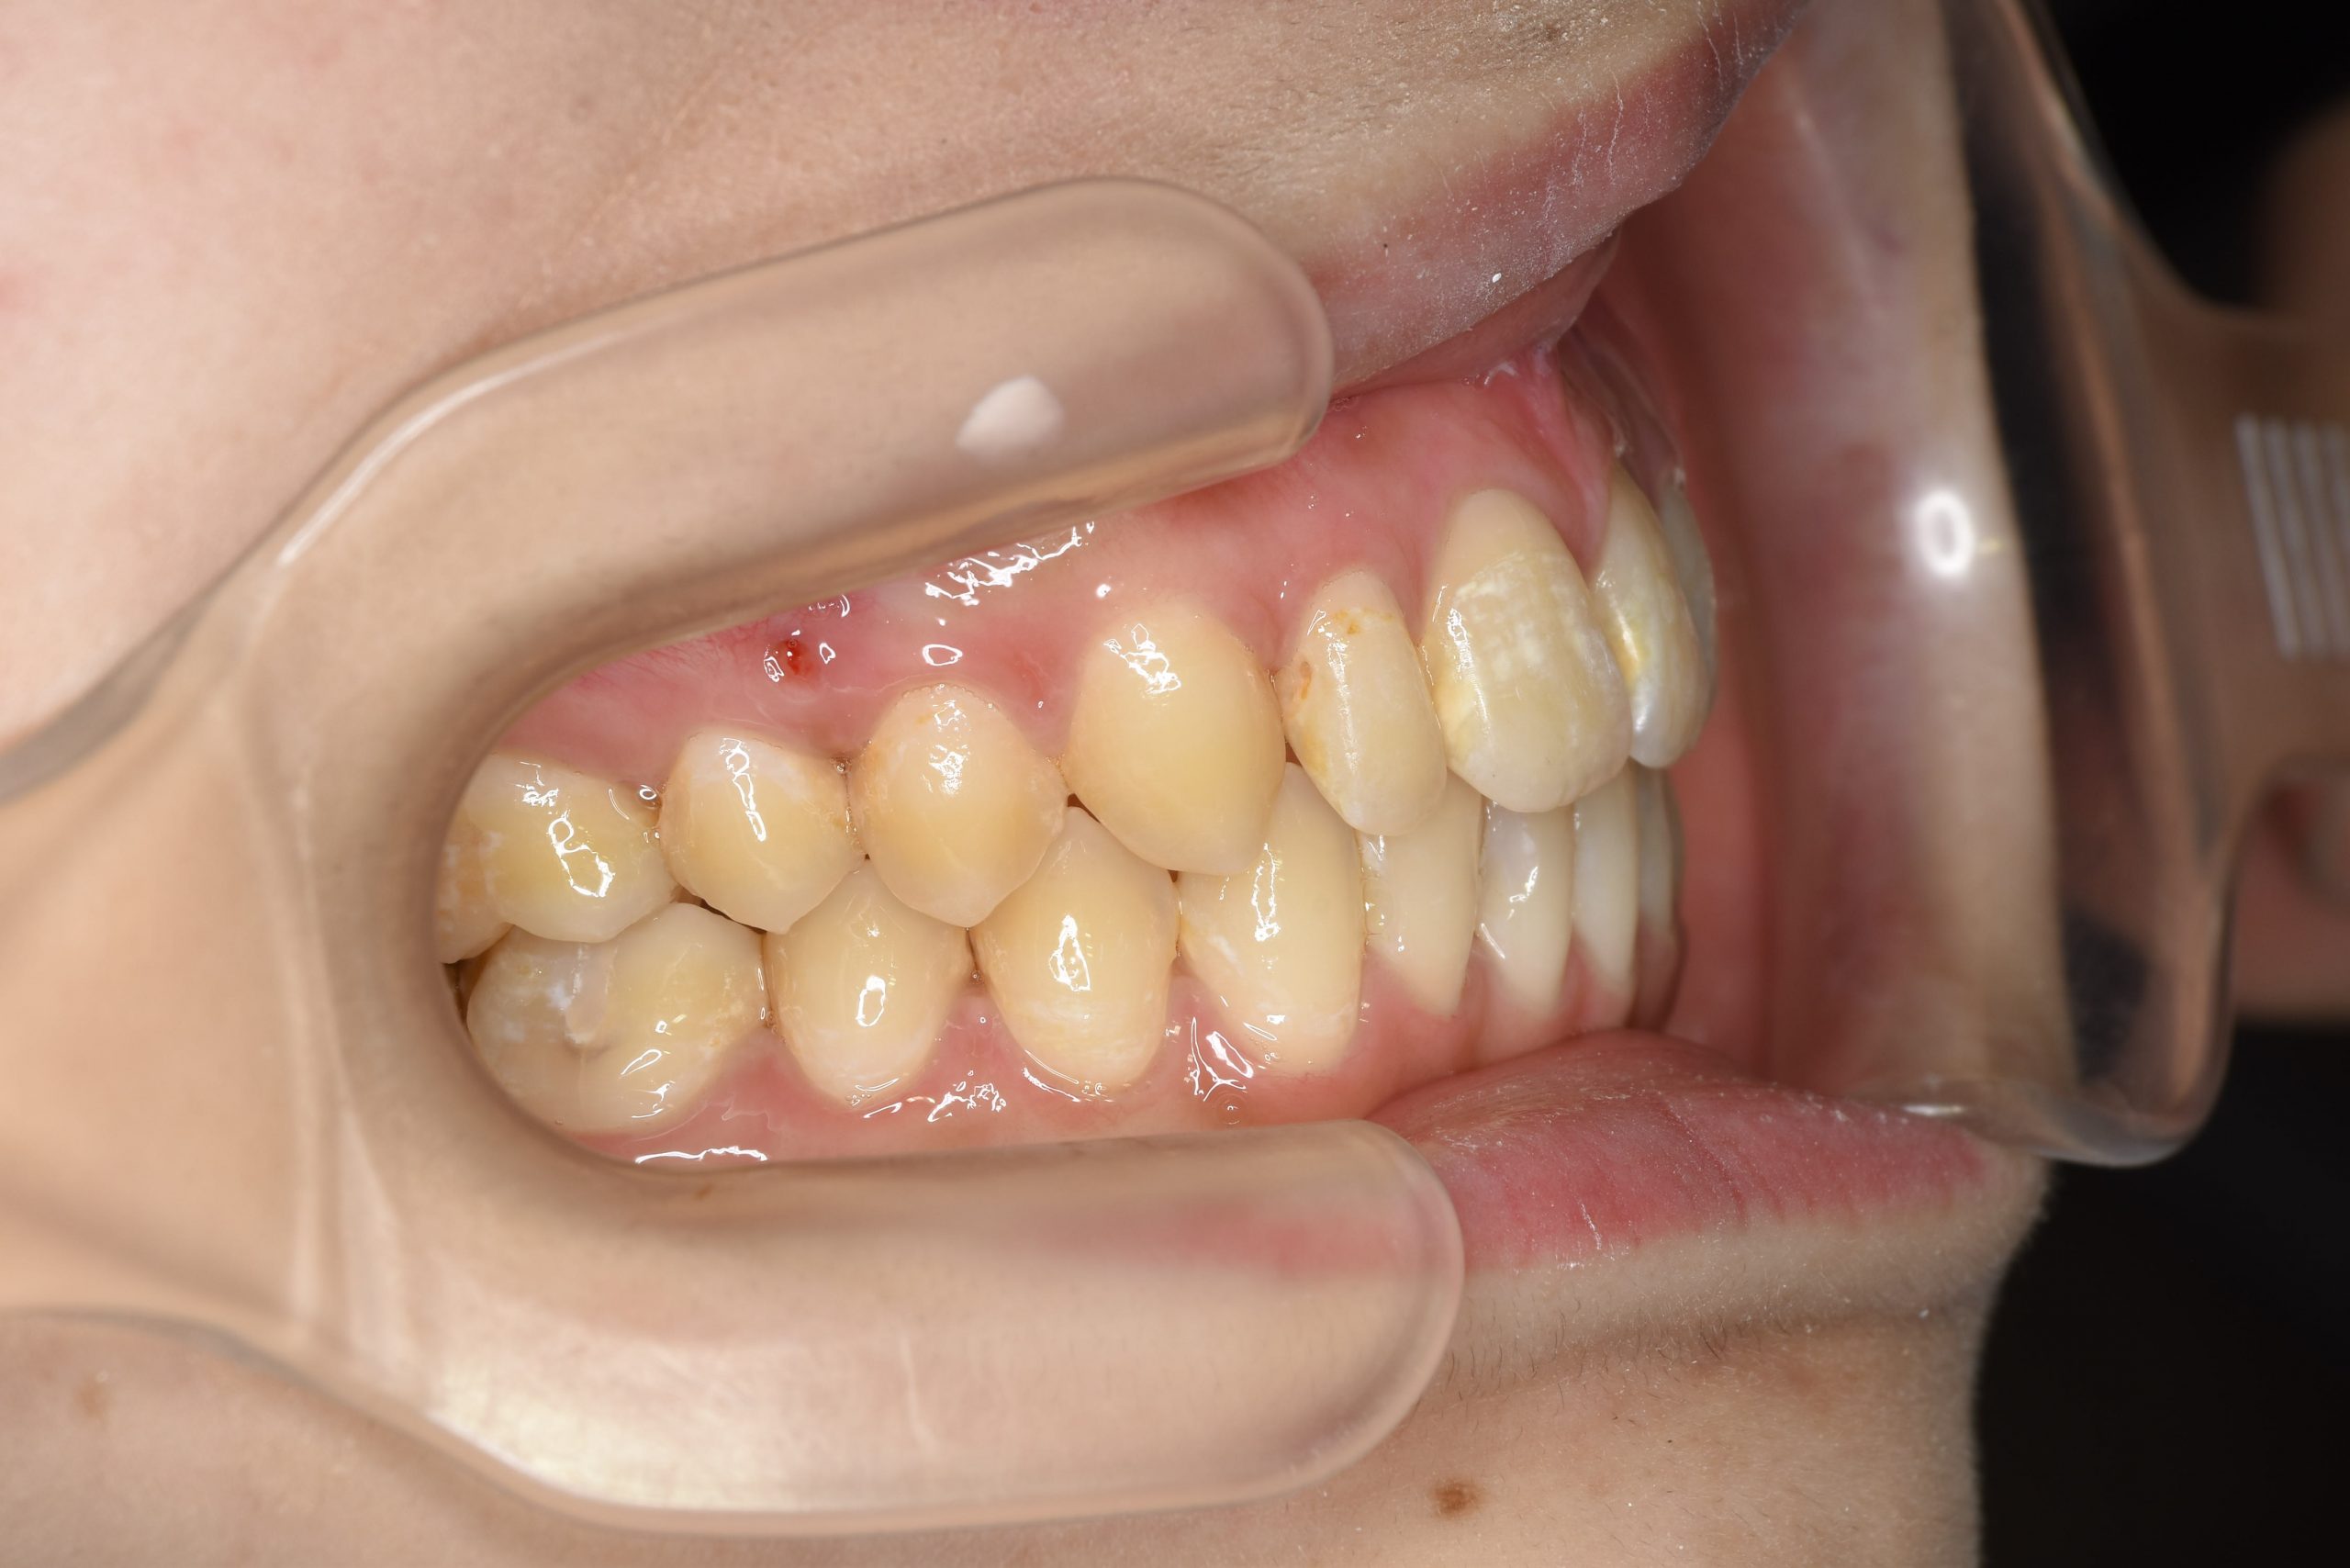

ビフォー

ワイヤー矯正治療|症例_032

主訴 歯並び|かみ合わせ

施術内容 MSEと下顎リンガルアーチを用いて上下顎骨を拡大した。

その後マルチブラケット装置を用いて非抜歯で歯牙を配列し良好な咬合を獲得した。

吸指癖と鼻閉症状は改善した。